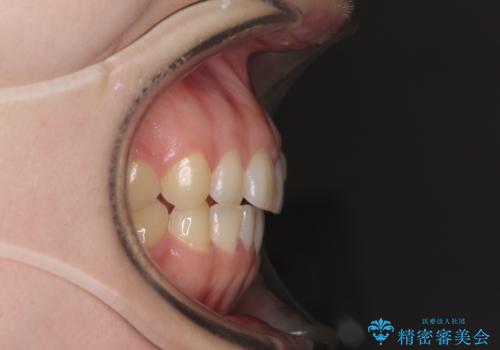

気になる残存乳歯と八重歯 ワイヤー矯正を併用したインビザライン治療

- 八重歯を気にして来院された患者様です。

八重歯のために乳歯が残存していたため、乳歯を抜去して八重歯となっている犬歯を歯列に収めることとしました。

八重歯の移動量が多くなるため、インビザラインと併用してワイヤー矯正を行い、八重歯を改善した後に、上下歯列をインビザラインで整えることとしました。

犬歯は歯根が長くて太いため移動に時間がかかる上に、周囲の歯が八重歯に寄ってきてしまうため、仕上がるまでに期間がかかりました。